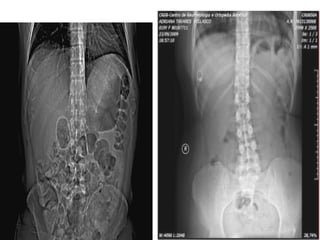

TOPOGRAMA

DECÚBITO DORSAL

BRAÇOS PARA CIMA

ABDOME TOTAL

ABDOME SUPERIOR

PELVE

PROGRAMAÇÃO

• Topograma.

• Início e fim dos cortes.

• Orientação: caudocranial

ou craniocaudal.